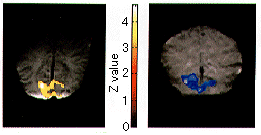

図2 右視放線梗塞(白矢印)による左同名半盲症例。チェッカーボードパターン視覚刺激を用いたfMRI。右V1には有為な賦活は認められていないが、右V5(矢頭)に独立した賦活が確認される。

(原論文1より引用)

図2は右側頭葉の動静脈奇形の経過中右視放線の障害から左同名半盲を呈した症例である。視覚刺激を用いたfMRIにて左一次視覚領野(V1)から連続性に広がる後頭葉の賦活が認められる。一方、右V1には有為な賦活は認められていないが、右側頭後頭部のV5領野に独立した賦活が確認される。すなわち、チェッカーボードパターンと言った動きの映像刺激では視放線以外の経路でV5の賦活化が行われていることが証明される。

図3 光刺激を用いた幼児のfMRI。生後7週の幼児(左図)では光刺激に伴い後頭葉視覚領野に信号上昇が認められるが、生後8週の幼児(右図)は信号低下が生じる。(原論文1より引用)

新生児から幼児に光刺激を用いたfMRIを行うことで、大脳皮質の発達過程の評価が可能となってきている。単純な光刺激に対して生後7週までの新生児から幼児では視覚領野の信号は成人と同様に上昇するが、生後8週以上の幼児では信号低下現象が観察される(図3)。大脳皮質は発達過程において生後約2カ月頃に急激なシナプス数の上昇を示すことが知られている。負荷に対して信号低下が生じる生後8週以降の幼児では急激なシナプス数の増加により、刺激に反応する皮質領野において急激な酸素消費が行われることで局所脳血流量増加が代償し切れていないことが予想される。すなわち、幼児期にfMRIを行うことでシナプス形成という重要な大脳皮質発達過程の評価が可能である。